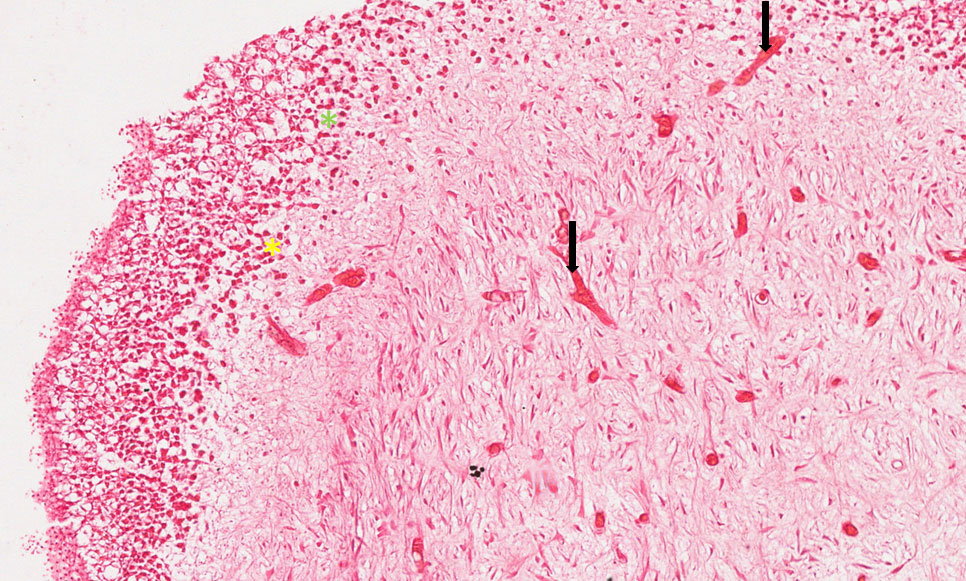

Corte histológico de dente com rizogênese incompleta, onde podemos observar a dentina externamente e a polpa na porção central. A inflamação pulpar é caracterizada pela presença de hiperemia, vasodilatação, associada à formação de exsudato inflamatório.

Observar o aumento de número de vasos na polpa (setas pretas), exsudato inflamatório com células inflamatórias especialmente linfócitos (asterisco amarelo), plasmócitos (asterisco verde) e macrófagos.